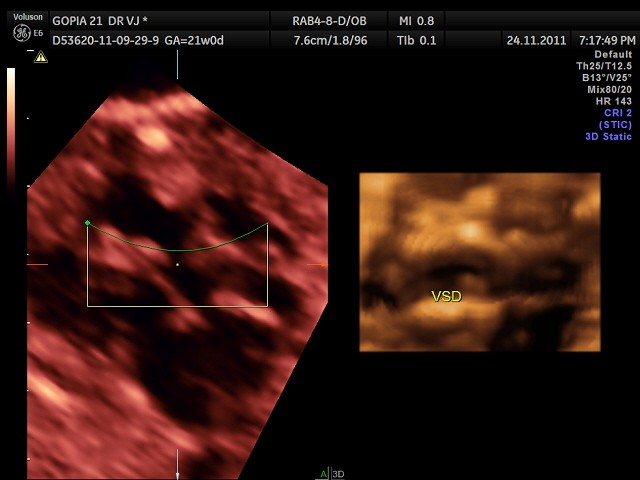

a 3 d reconstruction is given below